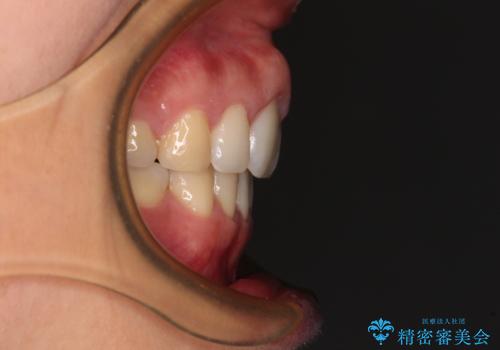

- 前歯の出っ歯と口元の閉じにくさを気にして来院された患者様です。

口元を積極的に引っ込めるために、上下左右の小臼歯4本を抜歯することとしました。

4本の歯を抜歯したことで、飛び出していた口元が引っ込み、横顔が大きく改善されました。